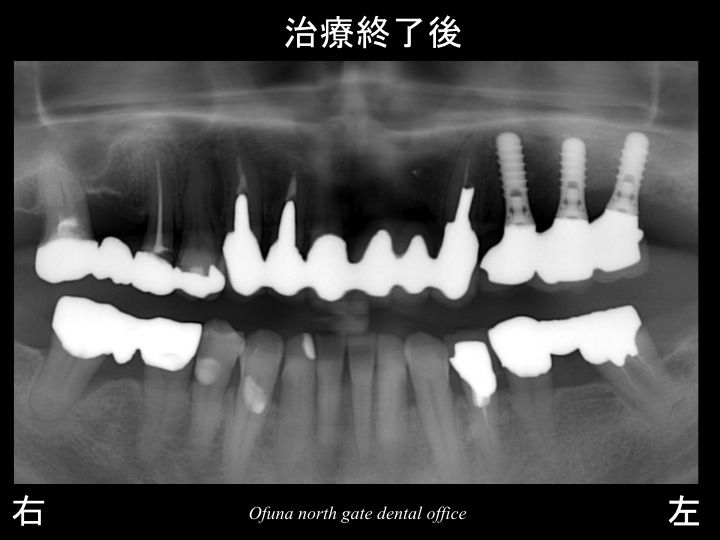

以下が治療後です。

このことにより左側で噛めるようになったことはもちろんのこと

残っている歯の将来性も高くなりました。